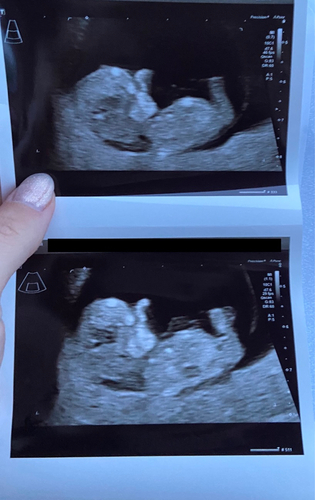

Nog niet eerder van gehoord, maar ik ben wel benieuwd. 13w1d

Beetje wazige echo om er iets van te zeggen. Kindje ligt ook iets gedraaid met het gezichtje. Als ik moet raden dan toch 馃挋

De nub was bij ons niet heel duidelijk te zien.. maar misschien iemand die een gokje wil doen adhv de skull theorie? Volgens mij is dit wel een mooi zij aanzicht!